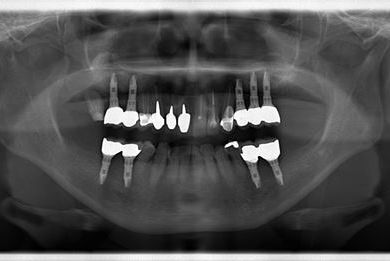

インプラントの症例写真 IMPLANT

骨再生スピードインプラント治療+セラミック治療

| 治療方針 | サイナスリフトにて上顎洞を拳上し、インプラント治療を可能にする。抜歯と同時にインプラント埋入を行い、治療期間を短縮する。 | ||||||||||||||||||||||||||||||||

| 治療内容 | インプラント9本(抜歯即日スピードインプラント、サイナスリフト)、ハイブリッドセラミッククラウン12本(ハイブリッドセラミック用土台3本) | ||||||||||||||||||||||||||||||||